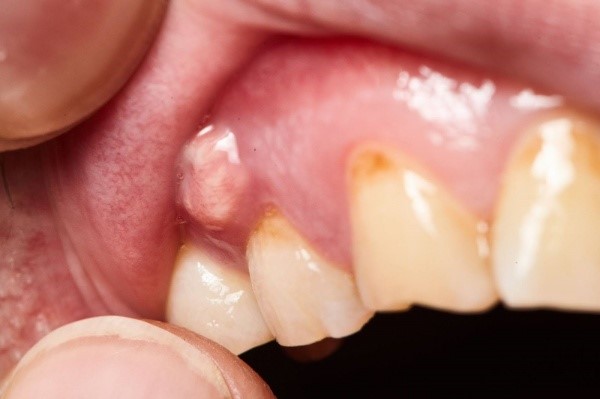

Viêm quanh cuống răng (viêm quanh chóp răng) là tình trạng vùng chóp của chân răng bị viêm nhiễm. Nguyên nhân chủ yếu dẫn đến bệnh lý này là do tủy răng bị chết hoặc tổn thương làm cho vi khuẩn lan dần xuống chân răng gây đau nhức dữ dội thậm chí là gây mất răng sớm.

(Vi khuẩn gây viêm tủy có thể thâm nhập sâu xuống chân răng gây viêm quanh chóp)(**)